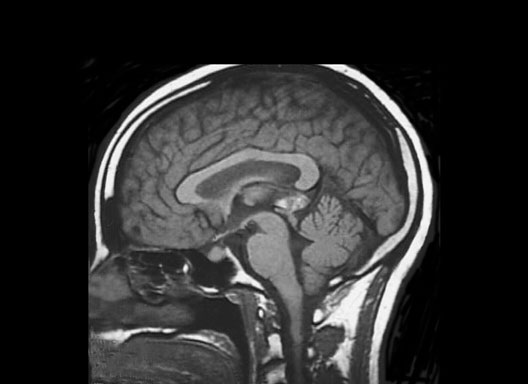

Head MRI Midline

Roll mouse over image to display labels.

1. Hard Palate

2. Nasopharynx

3. Sphenoid air sinus

4. Pituitary gland

5. Frontal sinus

6. Frontal lobe

7. Corpus callosum

8. Septum pellucidum

9. Parietal lobe

10. Fourth ventricle

11. Occipital lobe

12. Cerebellum

13. Sinus Confluence

14. Pons

15. Medulla Oblongata

16. Spinal Cord